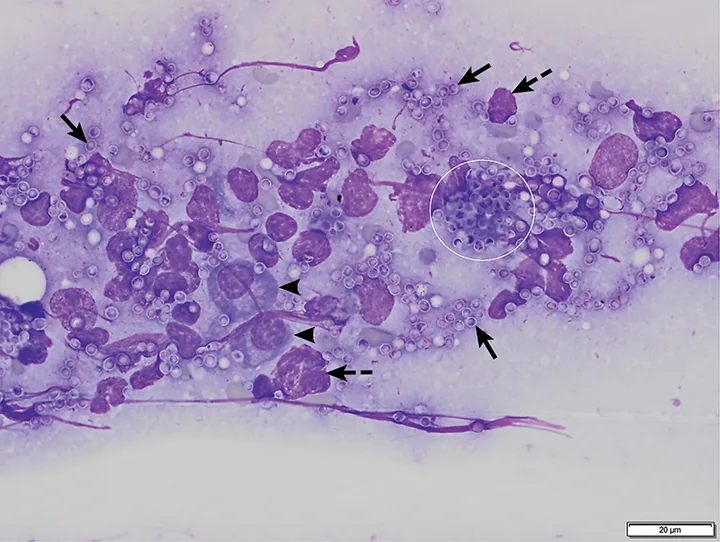

FIGURE 1

Bone marrow aspirate from a cat with pancytopenia. The numerous yeast organisms seen both extracellularly (arrows) and intracellularly within macrophages (circles) measure 2 to 4 µm in diameter and have a thin outer halo with eccentrically placed, basophilic, crescent-shaped nuclei. Organisms are consistent with H capsulatum. Modified Wright’s stain, 1000×. Scale bar = 20 microns

Bone marrow cytology of this cat (Figures 1 and 2) showed no bone marrow particles, rare marrow hematopoietic precursor cells (ie, megakaryocytes, myeloid and erythroid cells), and occasional plasma cells. Macrophages were markedly increased. Numerous round-to-oval yeast bodies measuring 2 to 4 µm in diameter were seen extracellularly and inside macrophages. The organisms had a thin outer halo with an eccentrically placed, basophilic, crescent-shaped nucleus.

Featured Image

FIGURE 2

Bone marrow aspirate from a cat with pancytopenia. H capsulatum yeast structures are seen extracellularly (arrows) and intracellularly within a macrophage (circle). Plasma cells (arrowheads) and nuclear material from lysed cells (dashed arrows) are also present. Modified Wright’s stain, 1000×. Scale bar = 20 microns